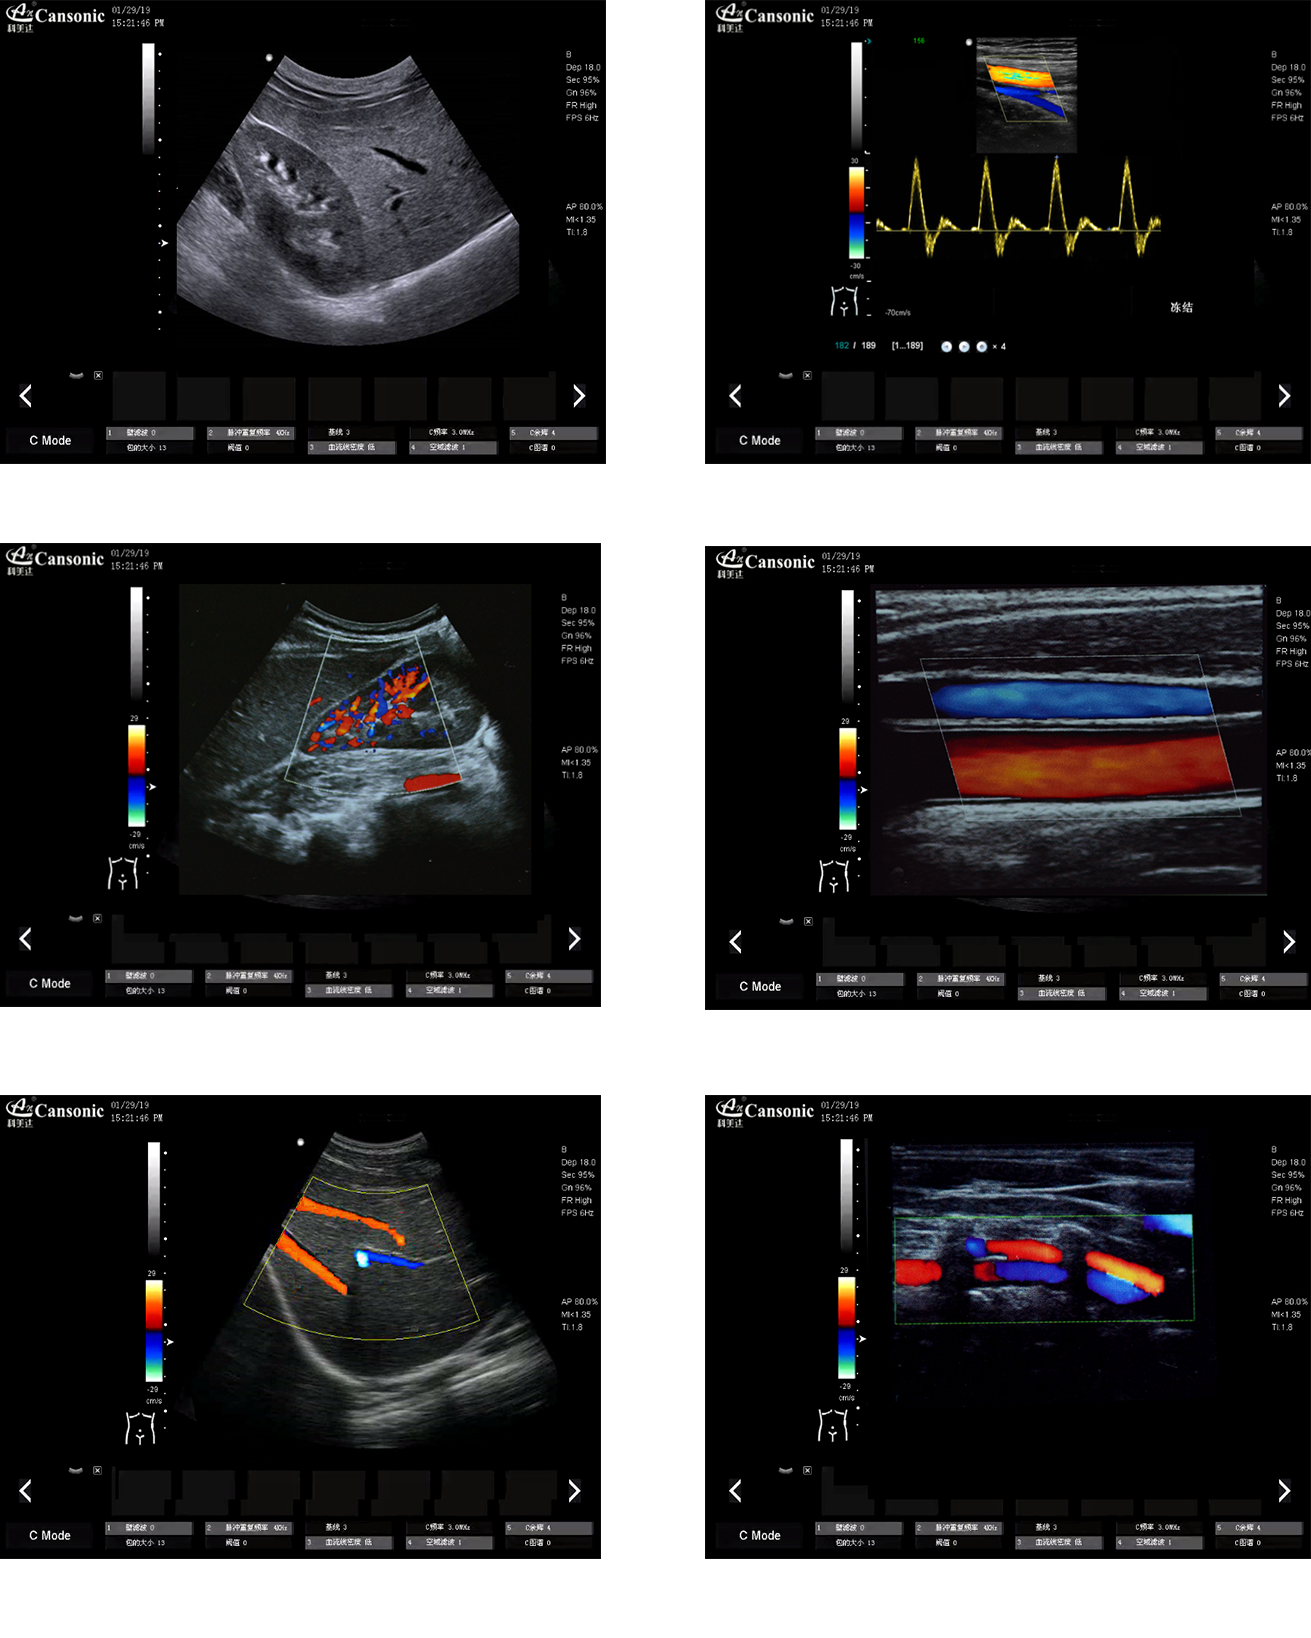

热博RB88K10图像实例